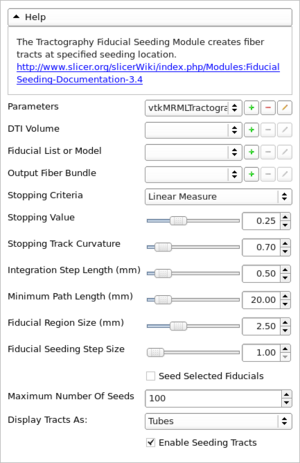

Documentation/4.3/Developers/ImageGallery

From Slicer Wiki

Home < Documentation < 4.3 < Developers < ImageGallery

Slicer

Modules